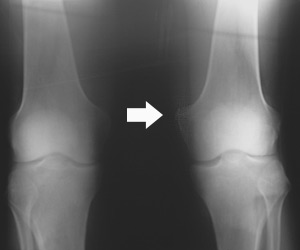

This happened to him on the slopes and he had to be taken to the local Orthopedic Surgeon by means of a stretcher, who made the diagnoses of partial medial collateral ligament tear and recommended RICE (Rest, Ice, Compression , and Elevation). At that point it took about 6 weeks for him to heal spontaneously. He is otherwise healthy and in good shape. His pain responds somewhat toCelebrex. In the past he was a heavy smoker till he quitted 10 years ago, his parents are healthy but he recalls his grandmother to have arthritis of the knees, requiring her to have a total knee replacement. On exam there was minimal edema or swelling with tenderness to touch to the medial aspect (inner side of the knee). His X-Ray showed Calcification or thickening of superior part (medical lingo: upper part ) of the Medial collateral Ligament, as if it was recalling it's unwanted memories. This condition is also known as Pellegrini-Stieda disease. X-Ray please note the the thickening and calcification of medial collateral ligament, due to a 20 year old ski accident.